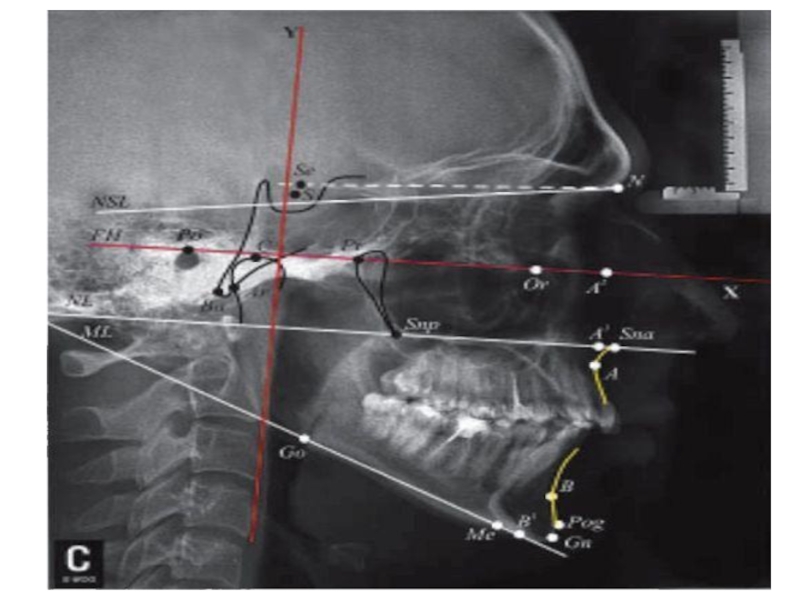

Слайд 7Ренгенологиялық зерттеуде жылжыған тістің периодонтальды саңылаудың кеңеюі, оның деформациясы, тіс альвеоласының

атрофиясы, тістің қисайған бағытында сүйектің қалатаны байқаймыз. Тіс түбірінің ұшында остеопороз шекарасын туындайды, оны кейде созылмалы периодонтит ошағымен шатастырады.